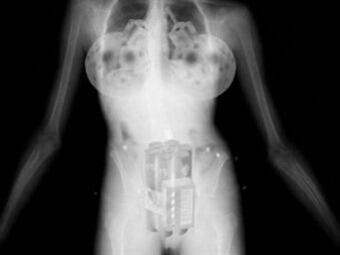

Según expertos en seguridad internacional hay una amenaza de Al Qaeda que someten a las mujeres a una cirugía de senos para ponerles implantes que están mezclados con líquidos inflamables, capaces de explotar con tal magnitud para derribar un avión

El experto en terrorismo Andy Oppenheimer, “hay un gran temor de que Al Qaeda esté perfeccionando el diseño de dispositivos que puedan pasar desapercibidos por los escáneres de los aeropuertos”